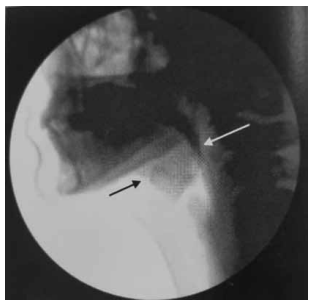

Observe, a seguir, a imagem de uma videofluoroscopia.

Enunciado 4258537-1

(Magalhães e Magnoni, Disfagia orofaríngea no adulto e no ambiente hospitalar)

Assinale a alternativa que corretamente a caracteriza.